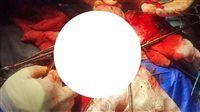

نجح الفريق الطبي بقسم جراحة المخ والأعصاب بمستشفى بلبيس المركزي بمحافظة الشرقية، في إنقاذ حياة طفلة سقطت من علو وأصيبت بكسر منخسف بالجمجمة، بعد إجراء عملية جراحية عاجلة لها.

وأضاف وكيل الوزارة أنه تم إجراء كافة الإسعافات الأولية والفحوصات الطبية والأشعات اللازمة فور وصول الطفلة إلى المستشفى، للحفاظ على حياة الطفلة، وعلى الفور تم تجهيز الحالة لغرفة العمليات، وقام الفريق الطبي بتنظيف الجرح ورفع الكسر المنخسف بعظام الجمجمة، وتفريغ النزيف أسفل فروة الرأس وأعلى الأم الجافية، مع وضع درنقة شفاطية، وذلك لحماية الخلايا المخية ومنع حدوث أي مضاعفات مستقبلية.

وأشار الأستاذ محمود عبدالفتاح مدير الإعلام والعلاقات العامة بالمديرية، إلى أن العملية تمت بقيادة الدكتور عيد النجار استشاري جراحة المخ والأعصاب ورئيس القسم بالمستشفى، والدكتور عمرو عيسى استشاري التخدير بالمستشفى، وأستاذة مشيرة كامل، وأستاذ راضي السيد هيئة تمريض العمليات، والحالة الآن مستقرة وبدرجة وعي جيدة، وجاري خروجها تحسن من المستشفى.